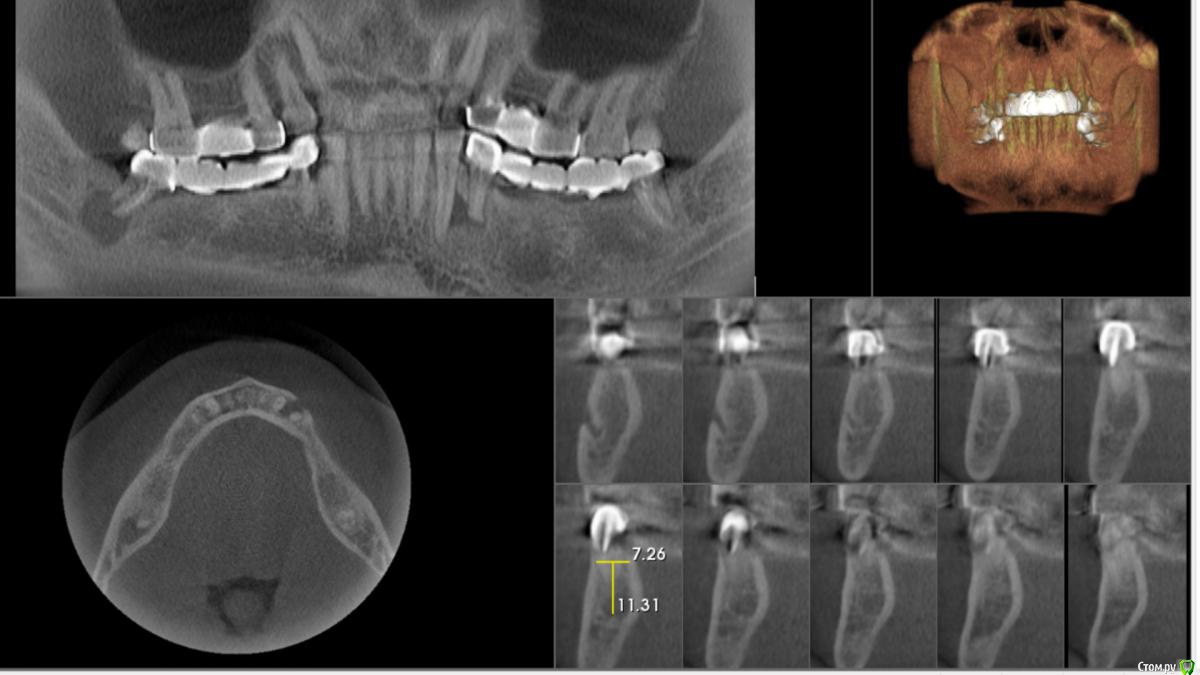

Foxtrot Опубликовано 27 мая, 2018 Поделиться Опубликовано 27 мая, 2018 Здравствуйте, коллеги. Пациент М 49 лет, планируется удаление зубов: 47, 44, 34 и установка 6-ти имплантов на н/ч. Смущает ситуация в области 34;44. Стоит ли идти на одномоментную имплантацию или лучше удалить и подождать? Ссылка на комментарий